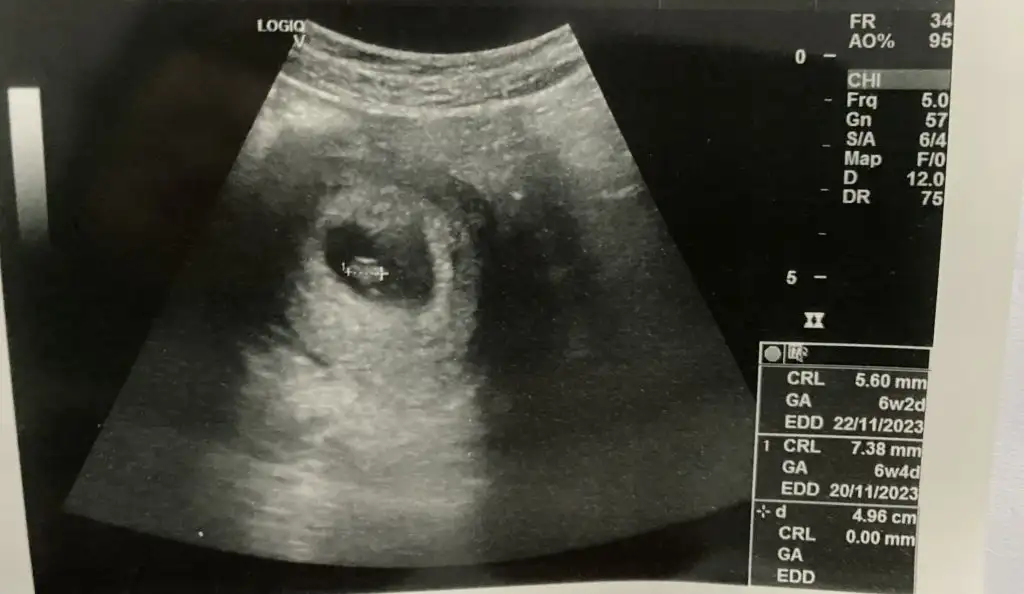

Benim de bu gün kontrolüm vardı. İkiz benim. Benim hiç kanamam olmadı ama doktor kesede kanama alanları gördü. İkiz gebeliklerde sıklıkla görüyoruz korkma dedi doktorum. İnşallah sağ Salim benimle kalırlar